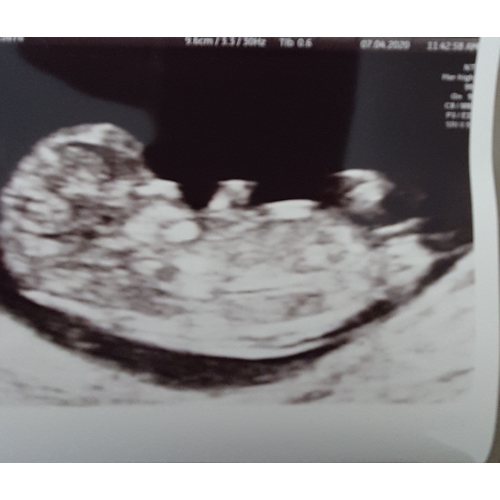

Nou, raad maar raak... haha.

Ben benieuwd wat jullie er in zien.

10w is helaas veel te vroeg voor de Nub theorie